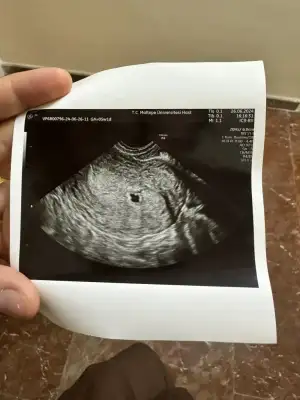

Benim de ara ara göğüs hassasiyetim oluyor öncesinde tek belirtim uçların sürekli belirginleşmesi olmuştu dikkatimi çekmişti tabi bilmiyorum bu bir belirti mi ama bende böyle bir değişiklik olmuştu5+4üm bende . Ben ilk göğüs hassasiyetinden anladım 3.haftalarda. Regl öncesi hiç göğüs hassasiyetim olmazdı.